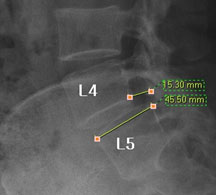

즉, 척추전방위증은 통증을 일으키는 원인질환(디스크, 협착증)을 치료하는 것이 척추 뼈를 더 이상 앞으로 밀려나가지 않게 하는 치료라고 볼 수 있습니다. 모커리는 뼈가 50% 이상 밀려나간 2단계의 척추전방위증도 비수술로 치료하고 있으며, 이러한 한방치료 효과를 객관적으로 검증하여 유명학회 및 논문에 계속해서 발표하고 있습니다.

모커리한방병원은 50% 정도 밀려나간 2단계의 척추전방위증 환자를 대상으로 약 3주간의 입원집중치료를 실시한 결과, 입원 시보다 80% 이상 통증이 감소되어 치료되었습니다. 통증 없이 걷는 시간도 약 3배 정도 증가되어 단기간에 수술 없이 높은 치료효과가 나타났다는 것을 대한침구의학회에 발표하였습니다. 50% 정도 밀려나간 2단계의 중증 척추전방전위증 환자이면서 심한 척추협착증 증상을 나타내는 환자를 치료한 결과입니다.